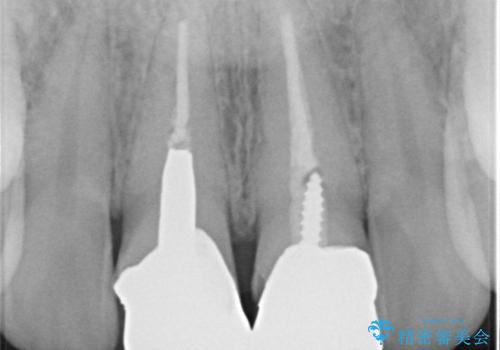

- 前歯のかぶせ物の変色を主訴に来院された患者様です。

根管治療からのやり直しはご希望されませんでした。

今回はe-maxクラウンで修復していきます。

- 仮歯:11,000円×2本 / e-maxクラウン:77,000円 合計176,000円費用は治療当時の料金となります